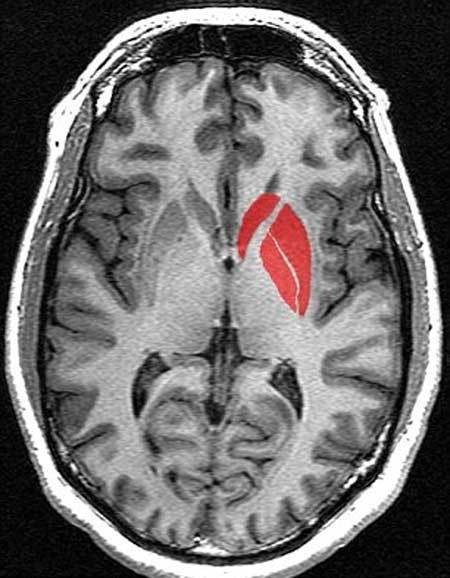

Bà Kuhn cho biết: "Chúng tôi khám phá ra rằng, khối lượng của vùng thể vân, vùng não gắn liền với việc xử lý khen thưởng và hành vi có động cơ, nhỏ hơn ở những đối tượng nghiên cứu thông báo xem nhiều phim khiêu dâm hơn. Thêm vào đó, chúng tôi phát hiện, một khu vực não khác góp phần cấu thành vùng thể vân và được kích hoạt khi chủ thể nhìn thấy kích thích tình dục, cũng ít hoạt động hơn ở nhóm thường xuyên xem phim nóng".

| Vùng thể vân (màu đỏ) trong bộ não của những người đàn ông thường xuyên xem phim "nóng" nhỏ hơn bình thường. Ảnh: Wikipedia |